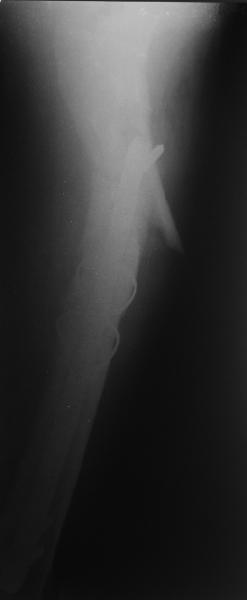

Изначально была выбрана не правильная точка введения стержня, в связи с чем в конце, я подчеркну, в конце операции произошло из-за напряжения между прокимальным концом канала бедра и стержнем разрушение в/3 бедра.

Проволока наложена потому, что при введении штифта не прошли эту зону римером и произошли сколы на концах отломков.

Зона раскола во время моей ревизии проходит по боковой поверхности как раз в зоне введения шеечного винта (картина как топор разрубил полено на две равных части, можа сделать КТ?)